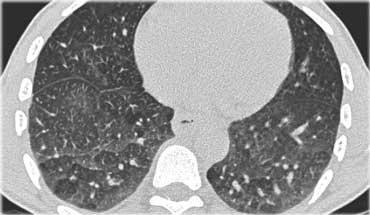

Bệnh nhân với Ung thư hạch bạch huyết lan tỏa.

Lưu ý phân bố khu trú của tổn thương.

Đặc điểm này có giá trị trong việc phân biệt Ung thư hạch bạch huyết lan tỏa với các nguyên nhân khác gây dày vách liên tiểu thùy như phù phổi hoặc sarcoidosis.

Ngoài ra còn có hình ảnh hạch to.

Bệnh nhân khác với Ung thư hạch bạch huyết lan tỏa có dày vách liên tiểu thùy (mũi tên vàng).

Kèm theo tràn dịch màng phổi (mũi tên xanh) và tổn thương di căn phổi (vòng tròn).